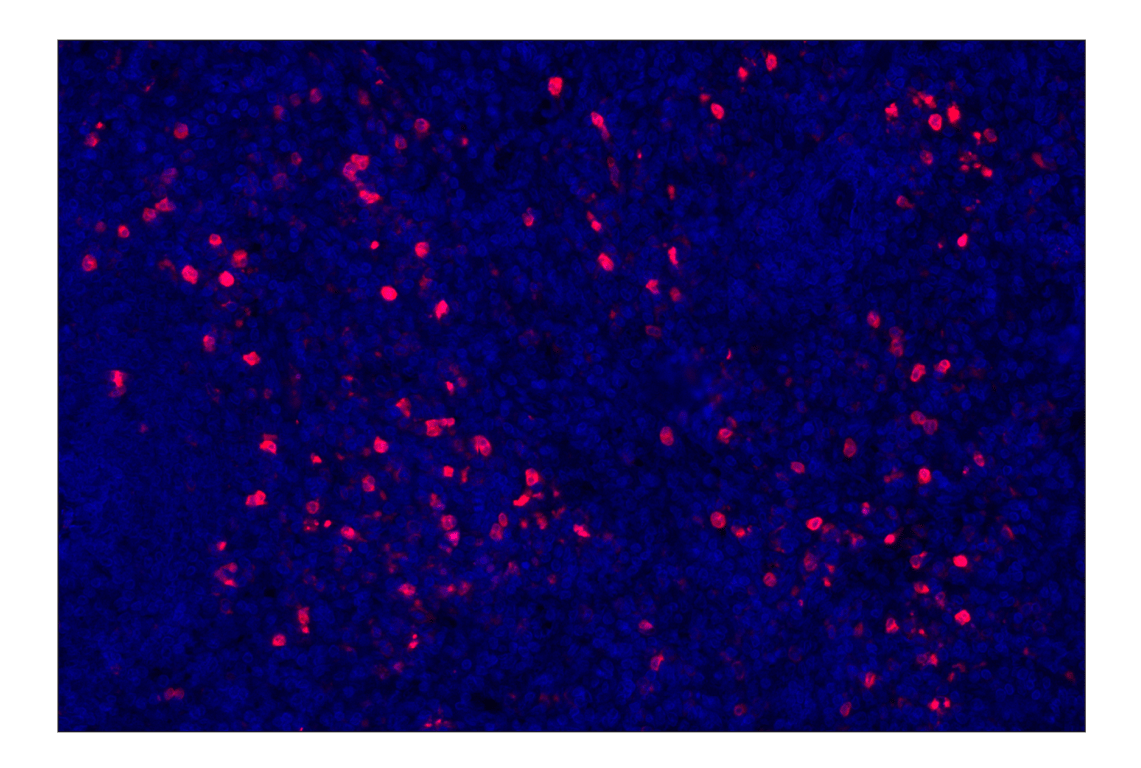

Eosinophil cationic protein (E6U5M) Rabbit Monoclonal Antibody (Alexa Fluor® 647 Conjugate) #15910

Immunohistochemistry (Paraffin) 1:100 - 1:400

Eosinophil cationic protein (E6U5M) Rabbit Monoclonal Antibody (Alexa Fluor® 647 Conjugate) recognizes endogenous levels of total Eosinophil cationic protein. This antibody does not cross-react with Eosinophil-derived neurotoxin protein.

Human